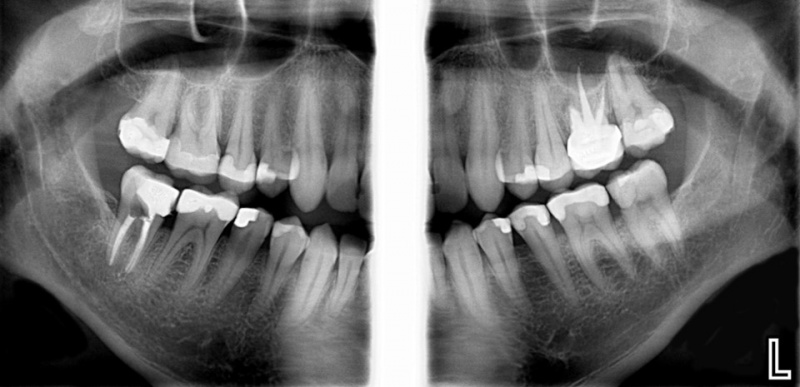

- Techniques for panoramic, periapical, and bitewing imaging.

- Panoramic Radiographs